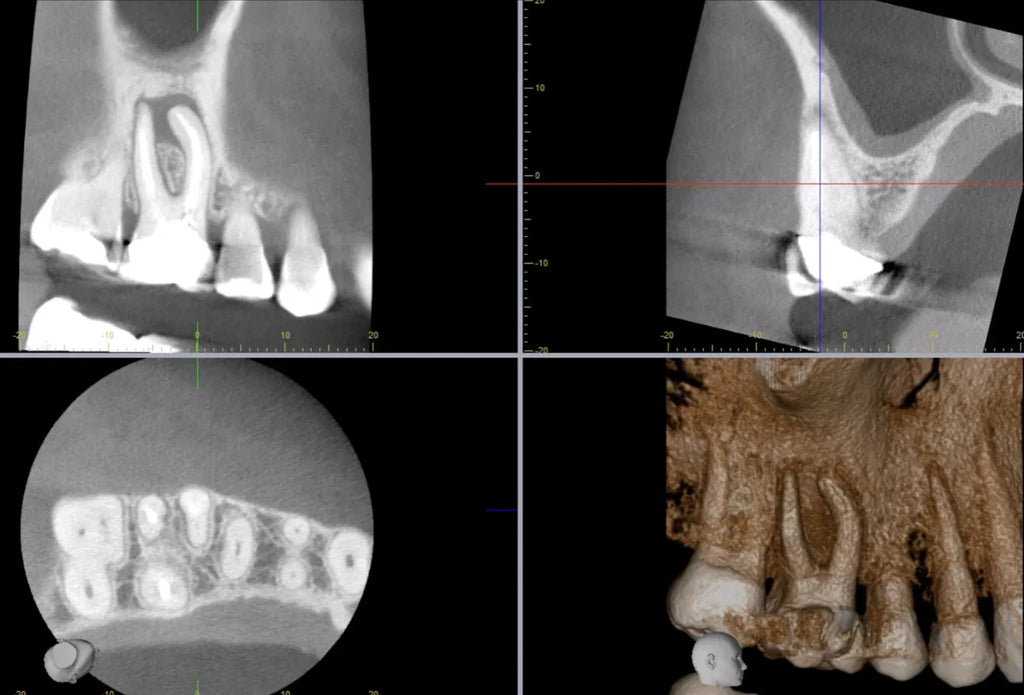

Level 1 & Level 2 CBCT Course with Lee Feinberg